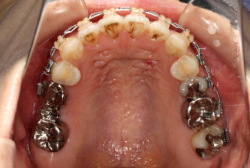

凸凹な歯並びのことを叢生といいます。矯正歯科に来院する患者様の主訴の中で、最も多いのが「配列の凸凹を真っ直ぐにしたい」というものです。歯の大きさと顎の大きさの調和がとれていないことが原因です。

凸凹を主体としたケースの場合、当院の平均治療期間は18ヶ月ですので、このケースは少し長めに経過しました。理由の一つは凸凹の程度がかなり重症だったと言うことですが、もう一つは、右下第2大臼歯が45度くらい前傾していたため、それを整直化させるために時間を要したと考えています。いずれにしても最終結果は大変よい状態と思います。

治療前は並びが乱れて見た目が悪いというのはもちろん問題ですが、歯科医学的に一番困るのは噛み合わせが悪いという点です。上下の犬歯(3番目の歯)は、上下的に離れた位置にあるため接触することができません。つまり歯としては存在していても、歯としては機能していないということです。

凸凹の強弱とは関係なく装置を最初に付けて数日は強い不快感・疼痛がありますが、数日~2週間で慣れてきます。特にこの症例のように凸凹が厳しい場合は、凸凹の歯の表面にさらに凸凹した装置が付きますので、非常に歯が磨きにくくなり虫歯や歯周病のリスクが高まりますので、歯磨き指導を十分に受けて、セルフメンテナンスに努めることが重要です。

本症例のように前歯部の凸凹が強い場合、歯間部歯肉が痩せて退縮する場合があります(ブラックトライアングル)。またマルチブラケット法全般に言えることは、口腔粘膜の違和感、金属アレルギー、歯根吸収などのリスクがありますので、事前に担当医より詳しい説明を受けて下さい。